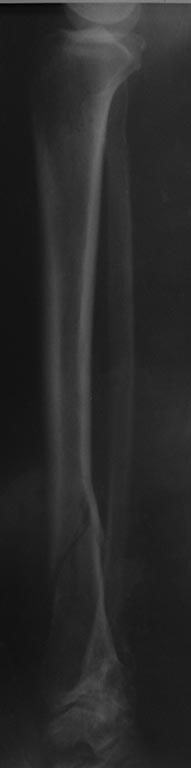

Пациентке 65 лет, получила травму 05.03.2015 г., упала на улице.

В анамнезе, примерно 20 лет назад был "перелом внутренней и наружной лодыжки левой голени", лечилось консервативно. Вопрос, забивать антеградно БИОС или же Артодезирование штифтом?

Качество снимка очень низкое, и оскольчатый перелом нижней трети большеберцовой кости легко спутать.

Судя по не очень качественному и неполному снимку - однозначно нужна корригирующая остеотомия большеберцовой кости.

Виноват, сначала решил, что речь идет о старом переломе голени. В идеале - остеотомия малоберцовой и остеосинтез большеберцовой кости пластиной в положении, нормализующем ось голеностопного сустава.

Артроз то тут при чем? Тем более артродез. Есть перелом - лечите перелом. Только снимки нормальные сделайте или КТ. А то так и до гланд с аппендиксом добраться заодно можно.

А мне видится перелом н/лодыжки со смещением,с подвывихом стопы кнаружи.